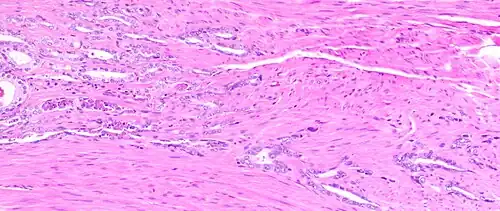

Histology of normal prostate, H&E stain, with benign features: Glands are rounded to irregularly branching, with an inner layer of epithelial cells surrounded by an outer layer of basal cells. They are surrounded by ample stroma. -

The prostate consists of glandular and connective tissue.[2] Tall column-shaped cells form the lining (the epithelium) of the glands.[2] These form one layer or may be pseudostratified.[4] The epithelium is highly variable and areas of low cuboidal or flat cells can also be present, with transitional epithelium in the outer regions of the longer ducts.[10] Basal cells surround the luminal epithelial cells in benign glands. The glands are formed as many follicles, which drain into canals and subsequently 12–20 main ducts, These in turn drain into the urethra as it passes through the prostate.[4] There are also a small amount of flat cells, which sit next to the basement membranes of glands, and act as stem cells.[2]

The connective tissue of the prostate is made up of fibrous tissue and smooth muscle.[2] The fibrous tissue separates the gland into lobules.[2] It also sits between the glands and is composed of randomly orientated smooth-muscle bundles that are continuous with the bladder.[11]